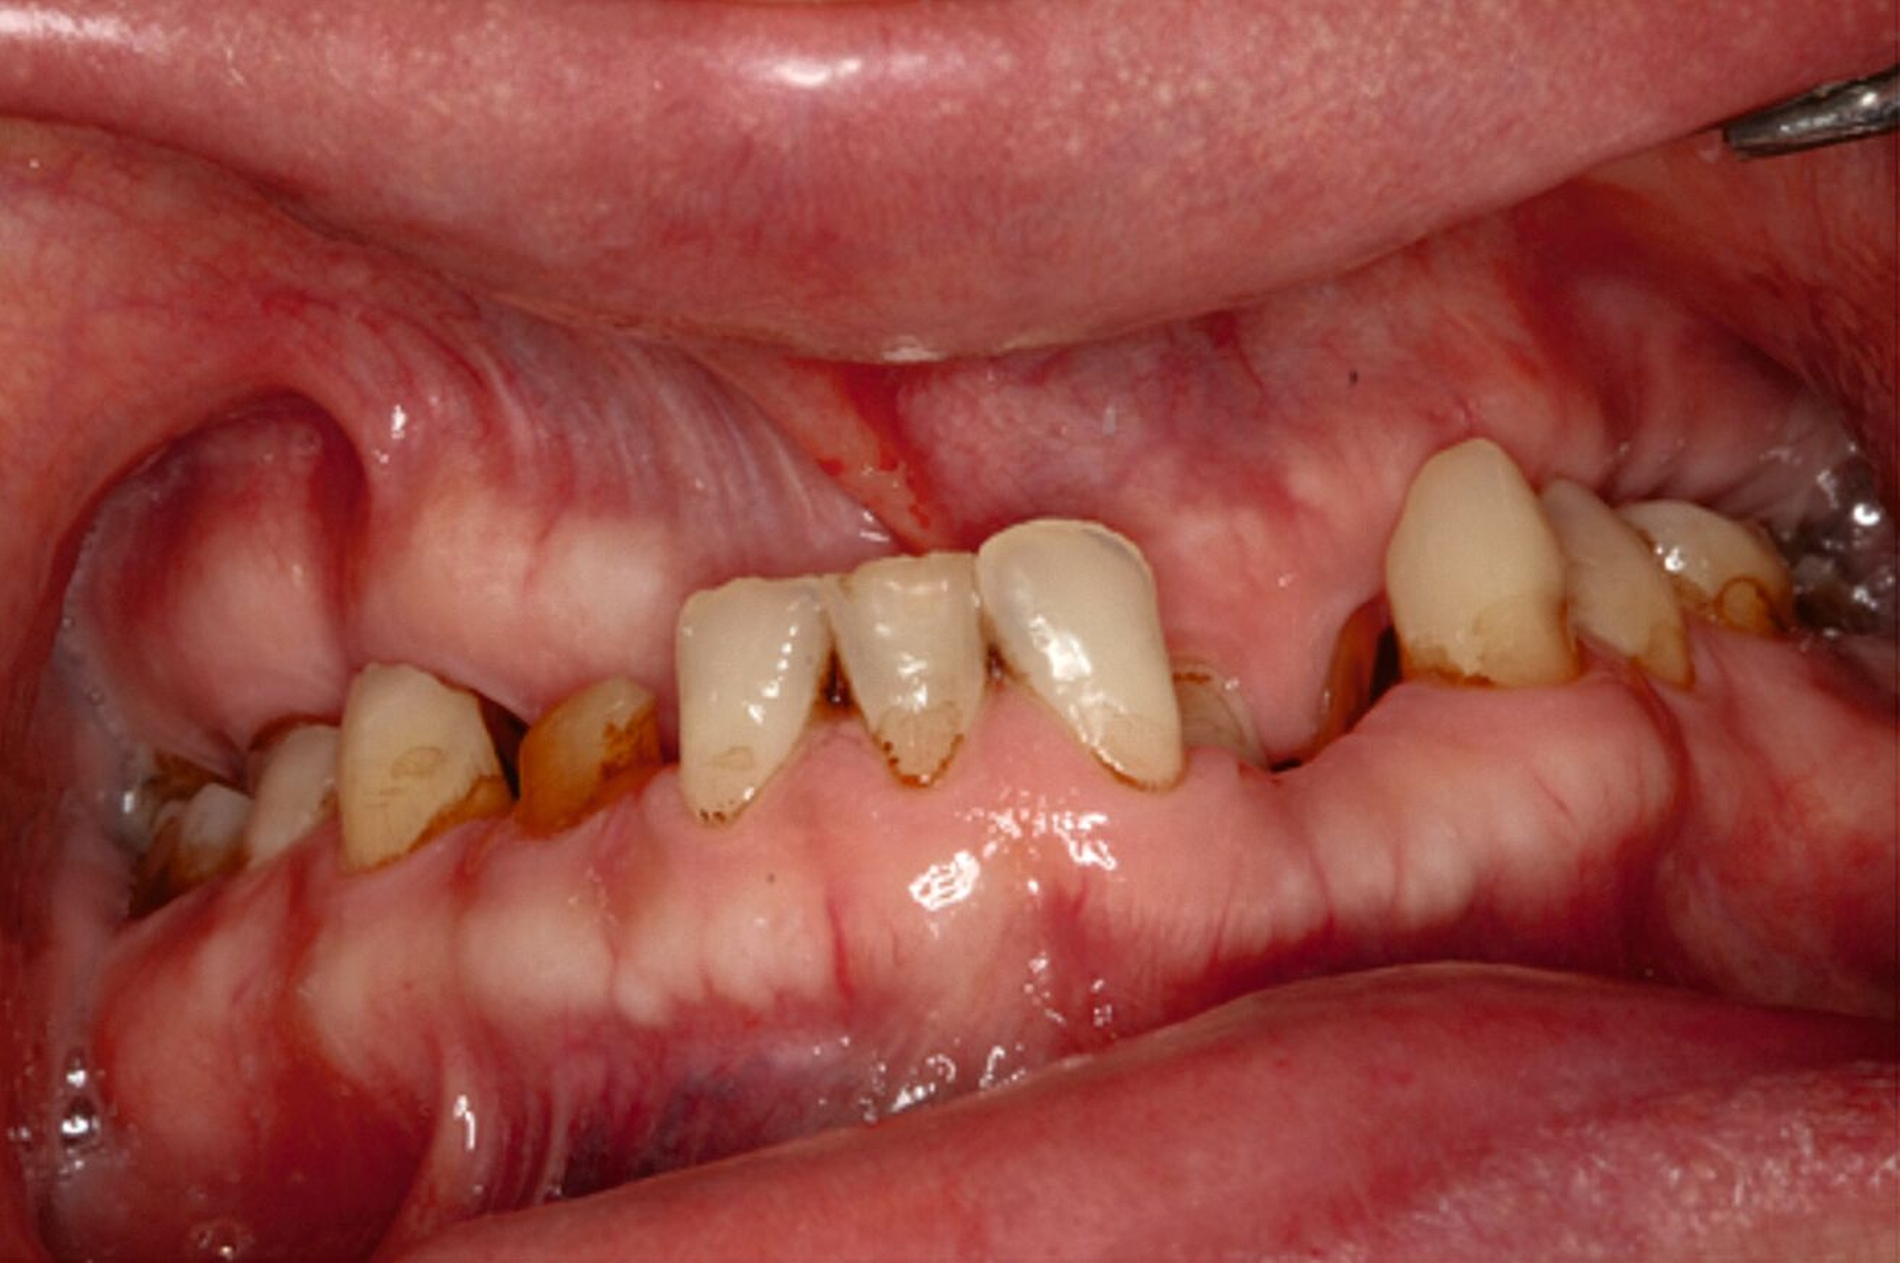

Eine mögliche und indizierte Umstellungsosteotomie wurde vom Patienten abgelehnt. Da seitens des Patienten eine Kopfbissstellung möglich war, wurde eine Bissumstellung und -hebung mit nur noch geringgradigem Vorbiss und anschließender Zahnimplantation in Erwägung gezogen. Begonnen wurde mit einer temporären Schienentherapie zur Neuorientierung der Bisslage (Abbildung 3). Da der Patient die angepasste Bisshebung tolerierte, wurde diese nach Entfernung der persistierenden Milchzähne 55, 53, 52, 62 und 83 temporär mittels einer Valplastprothese (Abbildung 4) als Interimsersatz im Oberkiefer gesichert.